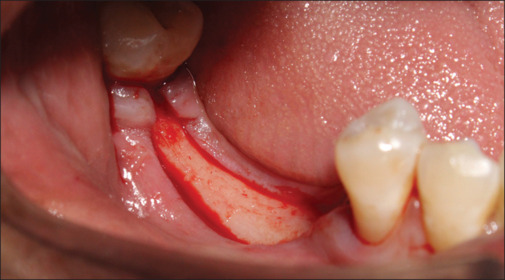

Settings and design: This research involved a sample of 15 patients who had partially dentulous mandibular arch. Within this group, a total of 30 implants were surgically placed. Specifically, each patient received two implants in the posterior region of the mandible, and the bone density in this area was classified as D2 type. In each patient, one implant was loaded with Zr abutment and the other was loaded with Ti abutment. The bone quality in the area of implant placement was Type D2. Two groups were created for this research. Each group consisted of 15 early loaded dental implants with customized Zr abutments and customized Ti abutments respectively.

Materials and methods: Hard- and soft-tissue changes were evaluated in both the groups. Evaluation of crestal bone loss (CBL) with cone beam computed tomography and SBI, PD and PESs were evaluated by various indices at 2, 4, and 6 months postloading.